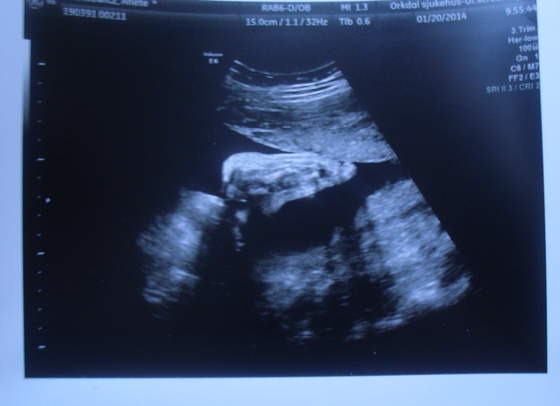

Moja Amelka to całymi dniami fika

i się właśnie zastanawiam kiedy ona śpi? mam nadzieję, że jak się urodzi to będzie spać więcej